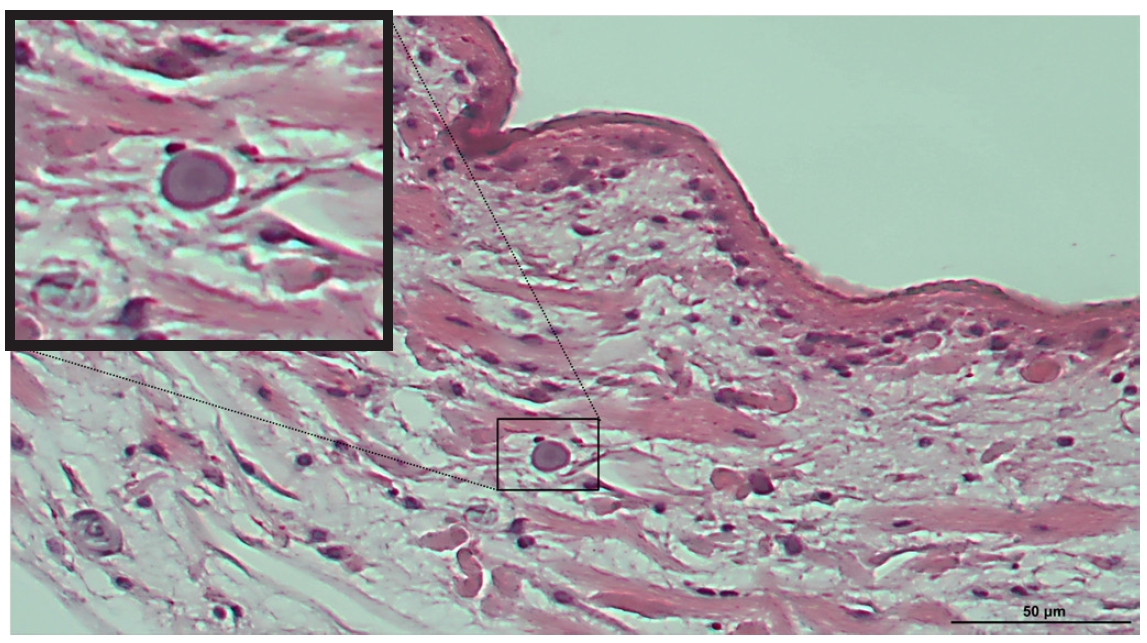

A fatal case of complex hepatic alveolar echinococcosis

Li Xin, Li Mengmeng, Yu Huixia, Zan Runna, Li Guojun, Shang Rongjian, Yu Jia

Parasites Hosts Dis 2026;64(1):98-103.

Published online January 22, 2026

DOI: https://doi.org/10.3347/PHD.25022

Hepatic alveolar echinococcosis (HAE), a life-threatening zoonosis, poses formidable surgical challenges when involving critical vasculature. Herein, we reported the periprocedural management dilemmas in radical resection for advanced HAE. A 58-year-old female visited the outpatient department presented with HAE. Imaging examination revealed extensive invasion of the hilum, bile duct, and several hepatic vessels, as well as left adrenal metastasis. The patient underwent right trisegmentectomy with left hepatic vein reconstruction, auto-transplantation, and adrenalectomy, with intraoperative Doppler demonstrating patent portal flow before abdominal closure. However, emergency thrombectomy and transcatheter thrombolysis were performed due to the abrupt occurrence of portal vein thrombosis 3 h after surgery. Despite intervention, the residual liver volume remained insufficient (approximately 28% of the standard liver volume), leading to progressive liver failure. The patient expired from multiorgan failure 9 days after operation. This case underscores not only the critical balance between radical resection and preservation of residual liver function in the surgical management of complex HAE, but also the imperative need to establish a comprehensive postoperative thromboprophylaxis.